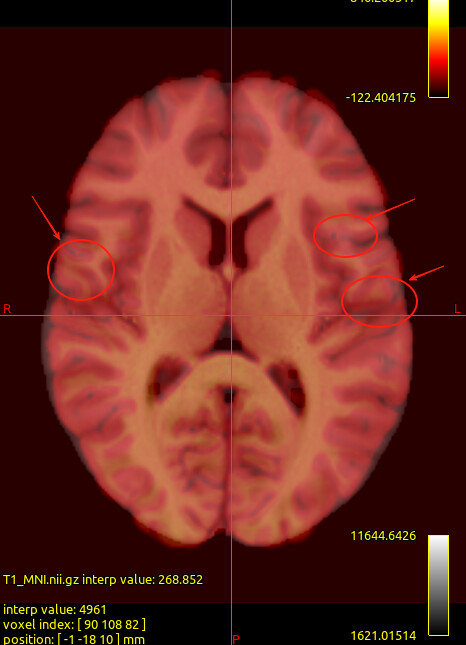

We noticed that the tck files already warped to MNI space are misaligned with the standard template in some sulcal and gyral regions. However, we also checked the registration between the T1 image and MNI space — even the T1 image warped to MNI space fails to align with the sulci and gyri of the MNI template. Nevertheless, the tck files in standard space show better alignment with the T1 image in MNI space. Can this be considered a good warping result? Figures are as follows.